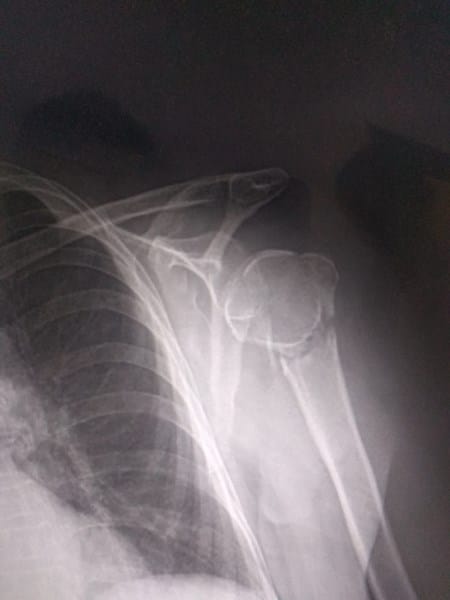

¿Rayos x, el humero está roto?

El hueso humero del brazo derecho está safado (dislocado), pero quisiera saber si la diafisis está rota, justo abajo de la epífisis.

Fue a causa de una caída, en caso de las radiografías, quisiera saber como es que se debería proceder con la "sanación, cirugía, curación"